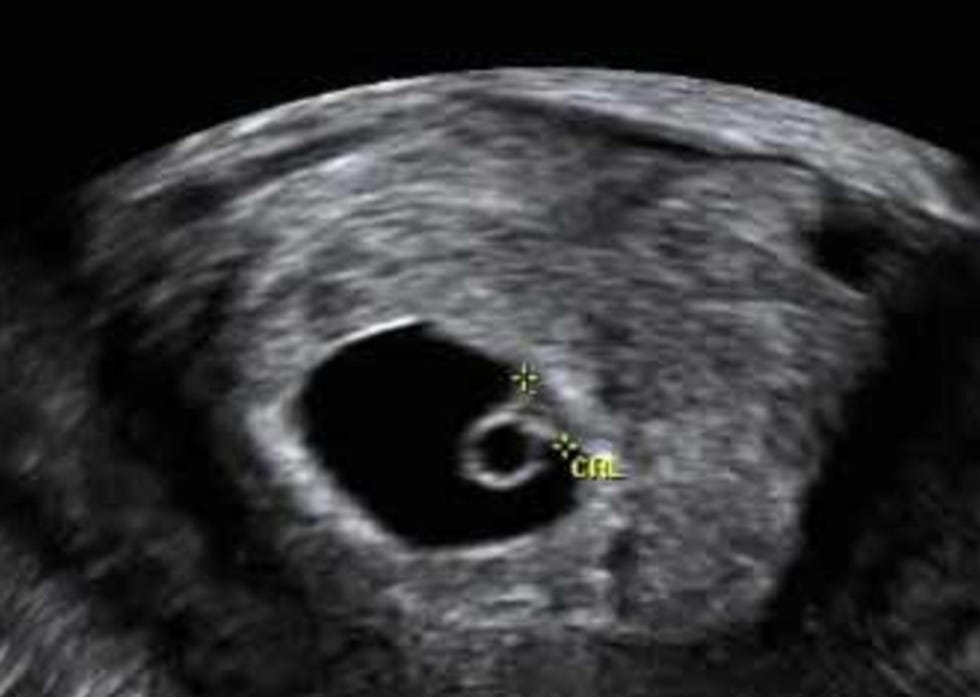

The bill Kasich vetoed is known as a "Heartbeat Bill" -- although that is a medically inaccurate misnomer. As the wonderful Dr. Jen Gunter points out, this would be more accurately termed a “fetal pole cardiac activity” bill. You see, although fetal "cardiac activity" can be detected at 6 weeks after conception, it's not at all what we think of as being a "heartbeat." In fact, heart tissue cells don't even begin to organize until about 20 weeks after conception.

There's no science behind these bills -- they're simply meant to tug at the heartstrings of non-fetal Americans, who will hear the term "Heartbeat Bill" and assume that the fetus is READY TO LOVE YOU, and is "this close" to being a fully formed person, when in fact it looks more like this at that stage: